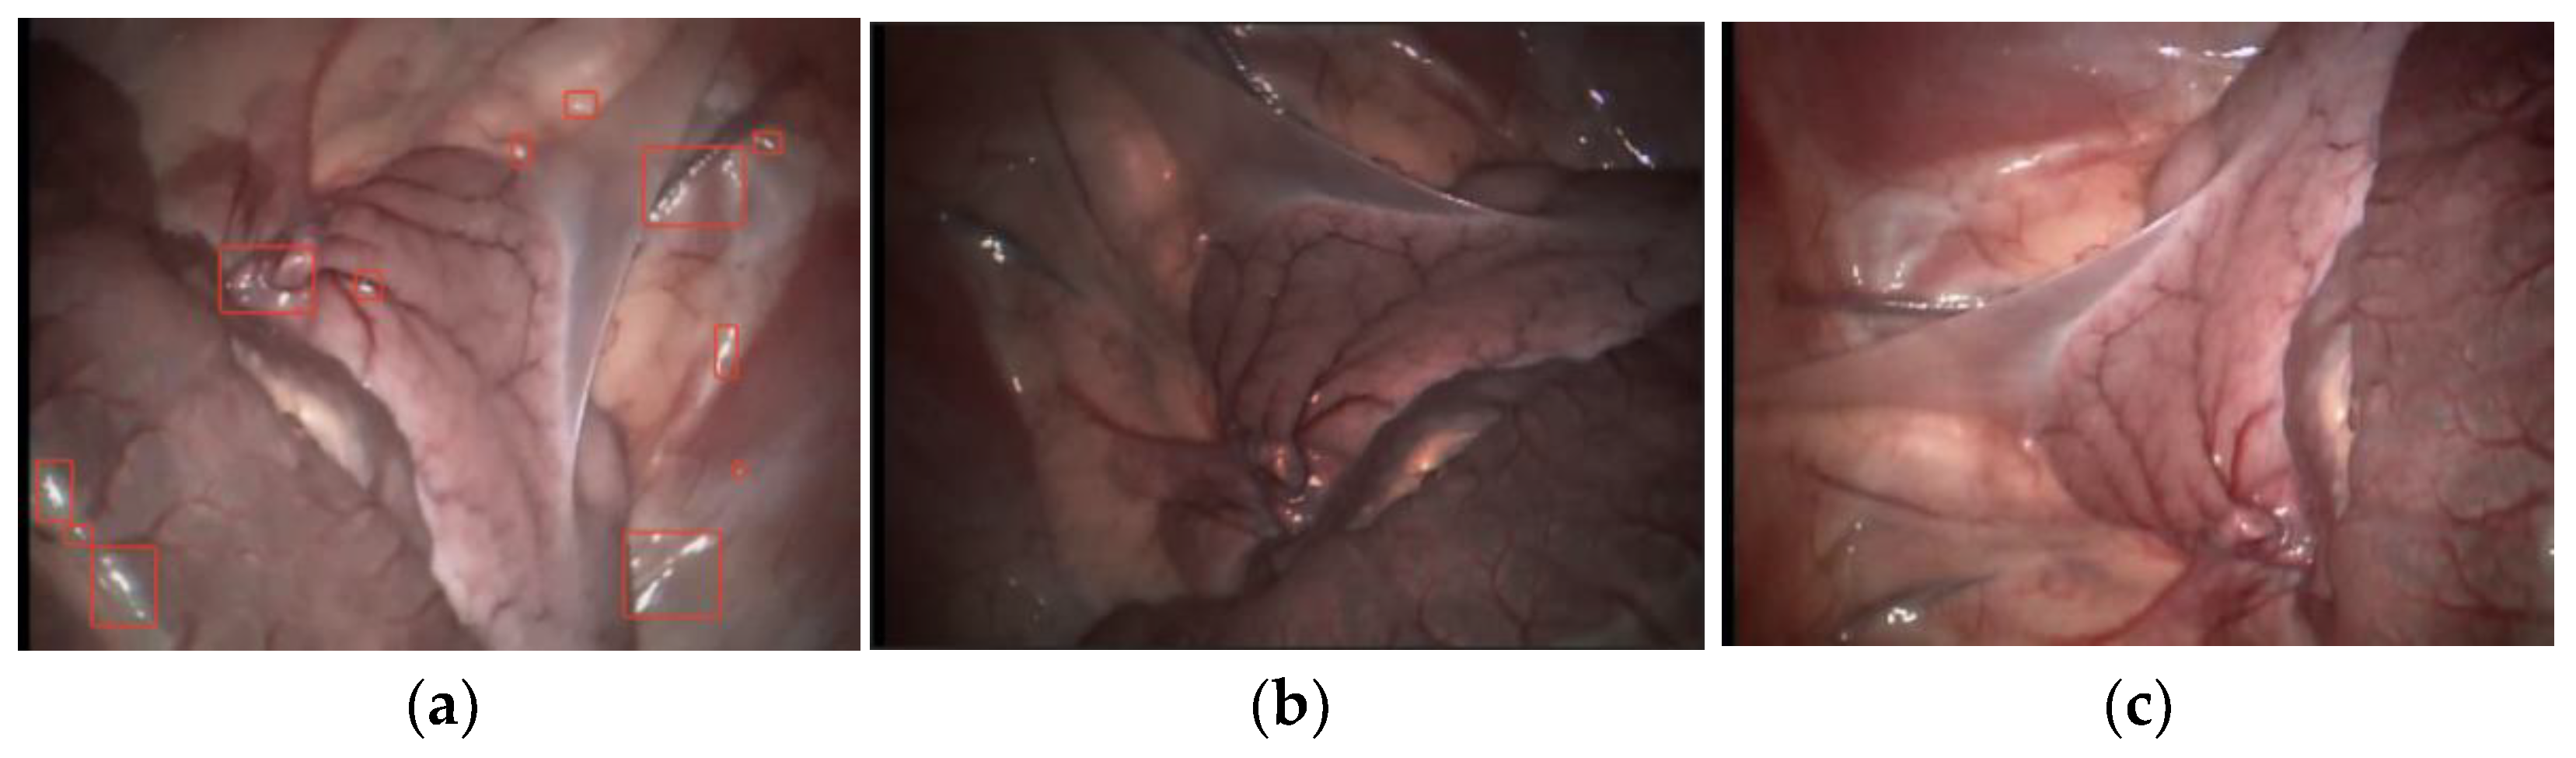

Due to the lack of features, repetition and noise in the abdominal cavity image taken by laparoscopy, a sudden change of illumination may occur during the operation, resulting in the reduction in visual recognition of abdominal image, as shown in Figure 2. Therefore, before laparoscopic pose estimation, it is necessary to preprocess the abdominal image collected by laparoscopy in order to extract more feature information from the abdominal image.

Figure 2. Abdominal images with different illumination. (a) Specular reflection; (b) Low-light image; (c) Partially low illumination.